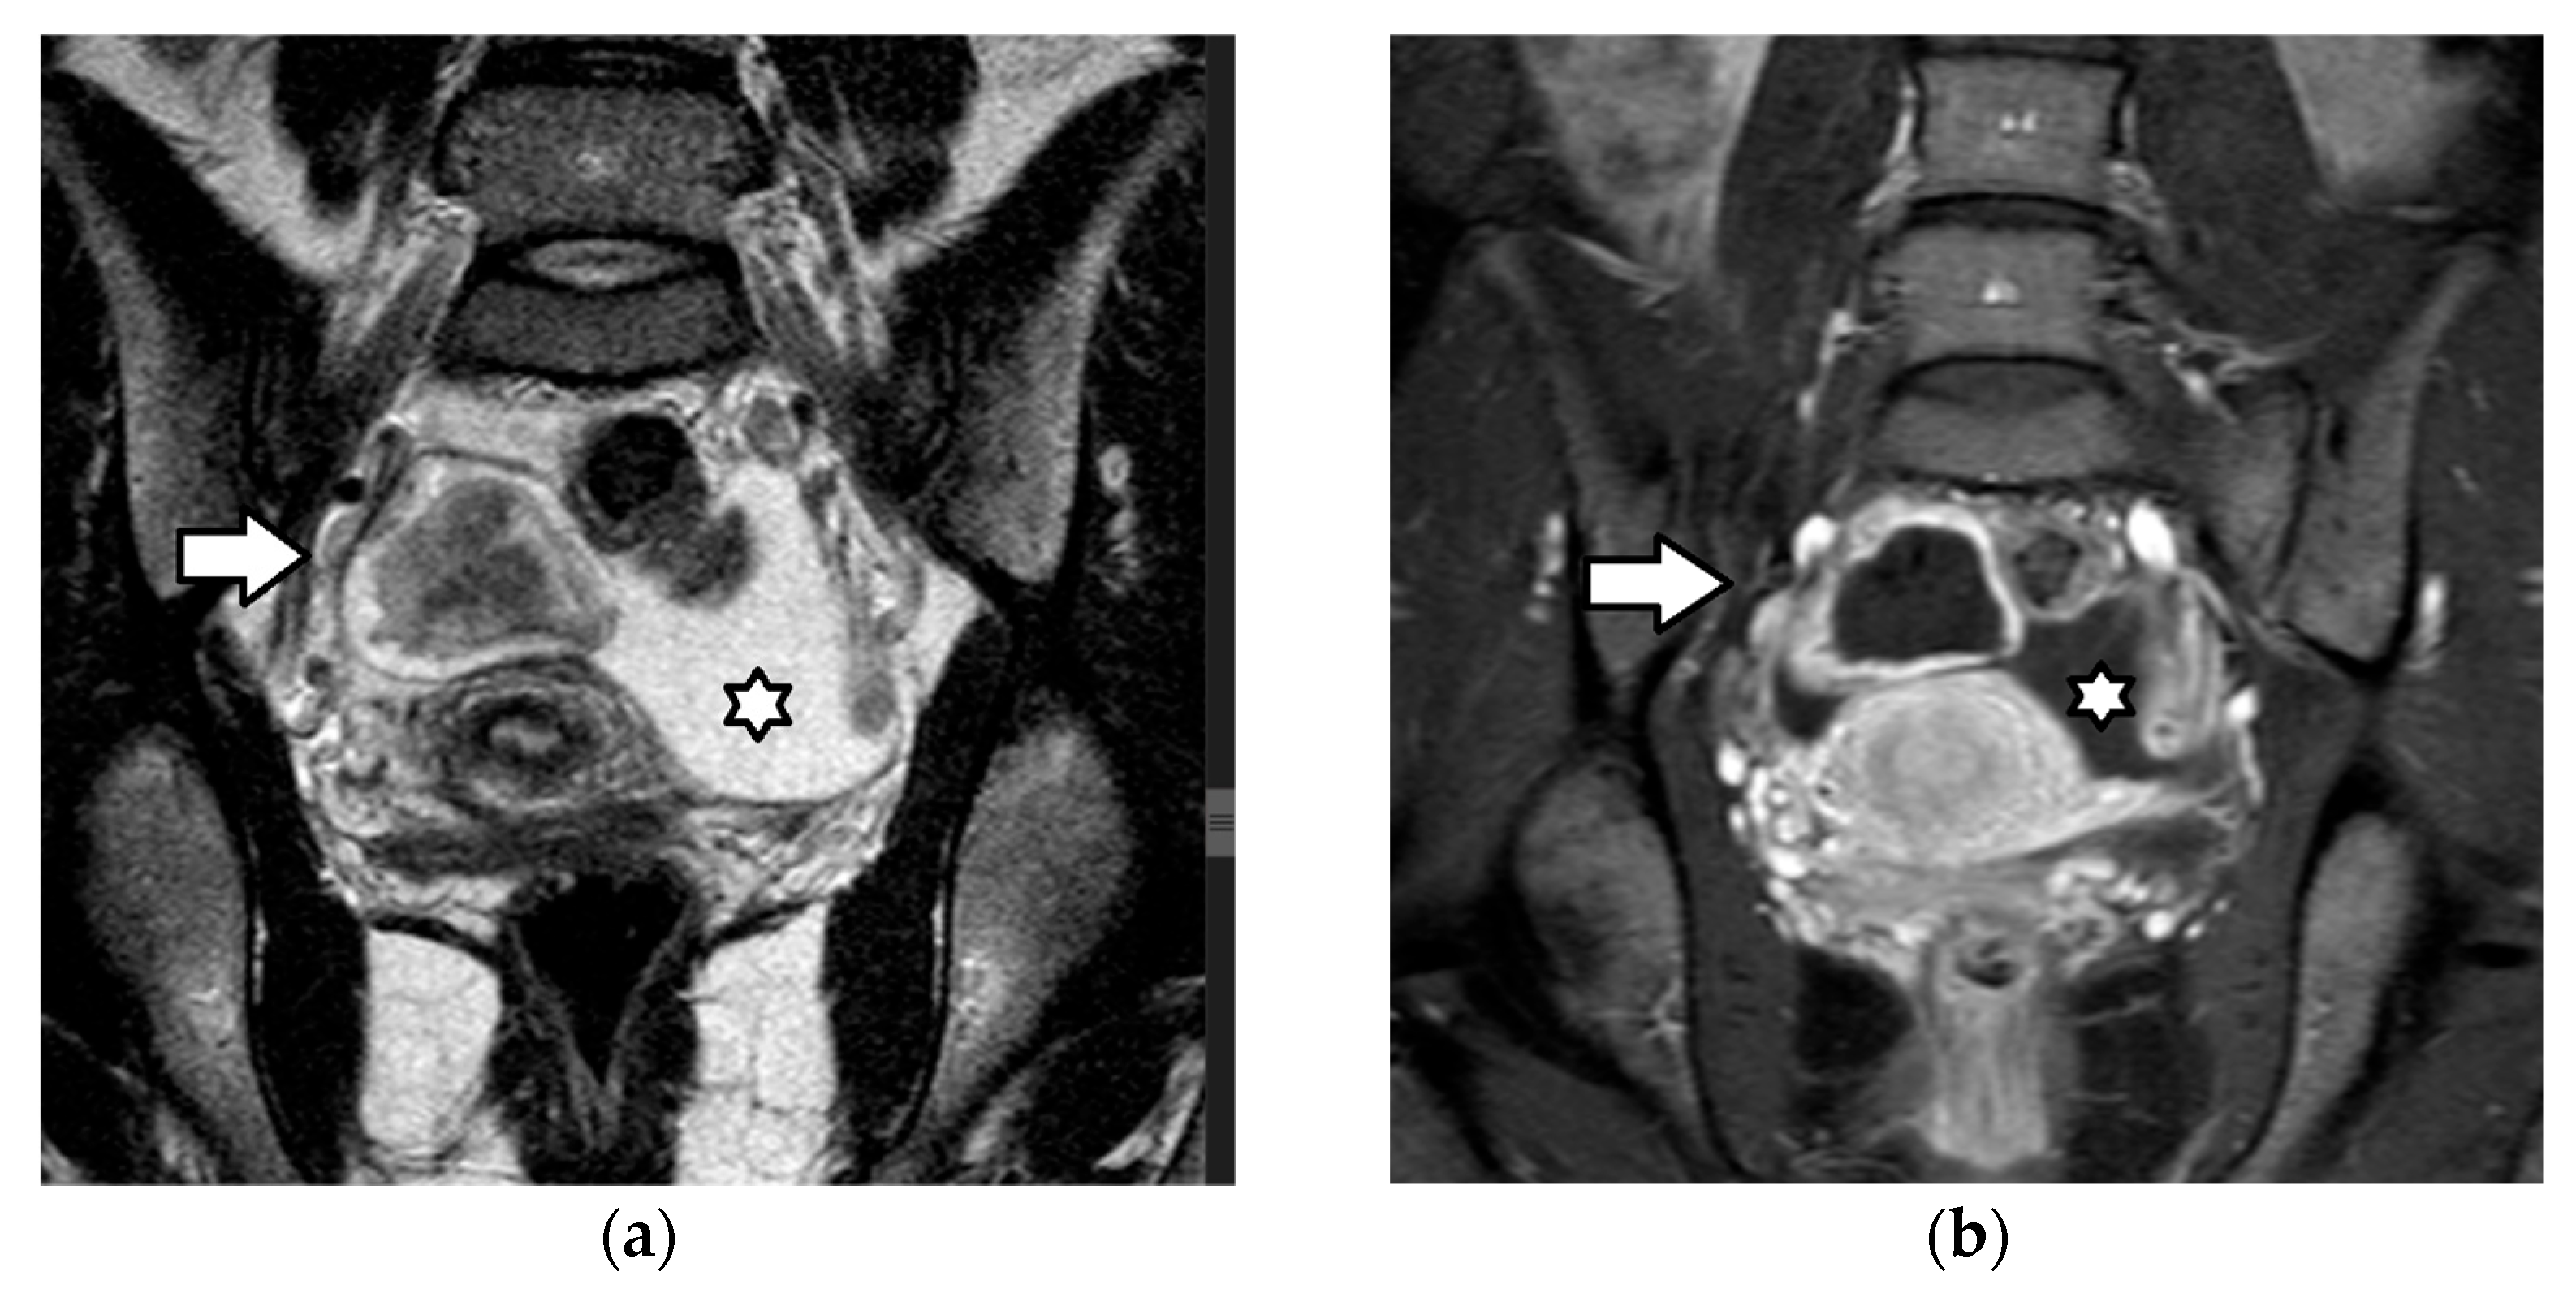

| Sertoli–Leydig cell tumor | 15% of SCSTs mean age: 14 years mostly unilateral secretes androgens: virilization secretes estrogens (rarely) association with DICER1 syndrome(moderately and poorly differentiated tumors) possible association with Peutz–Jeghers syndrome | moderately and poorly differentiated tumors: clinically malignant in 10% and 60% of cases, respectively often diagnosed at an early stage favorable prognosis recurrence rate: may be high | increased AFP (occasionally): poorly differentiated tumors with heterologous hepatocyte elements | nonspecific predominantly solid vascular tumor, with numerous peripheral or intratumoral cysts or cystic, with solid components MRI

|